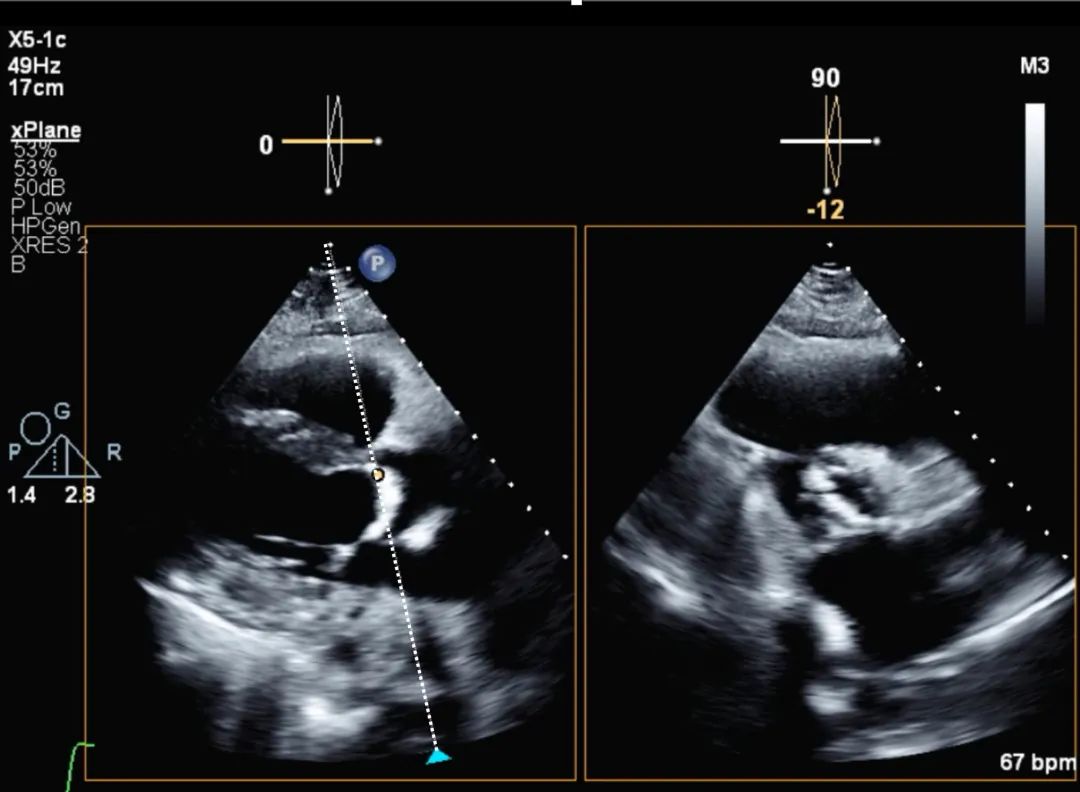

5、胸骨旁短轴切面:在主动脉瓣瓣尖于收缩期进行主动脉瓣面积直接平面测量(planimetry)——即描记法。使用双平面或三维成像技术可确保测量位于瓣叶尖端。如果测量未处于瓣叶尖端,则可能高估或低估主动脉瓣瓣口面积(aortic valve area,AVA)(图6)。

图6. 主动脉瓣瓣口面积的描记法测量

主动脉瓣瓣口面积的直接平面测量(即描记法)可采用双平面方式进行,此时光标需置于瓣叶尖端。然而,如果光标未完全精准地置于瓣叶尖端,可能导致直接平面测量结果产生误差。